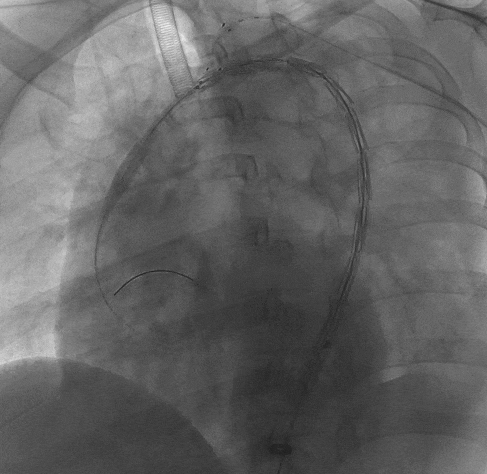

1、患者平躺后行全身麻醉手术,穿刺患者左肱动脉与右股动脉,并在左肱动脉置入穿刺鞘后,从右股动脉导入一根长鞘,长鞘里同走超硬导丝与软泥鳅导丝,自下而上地探索真腔,在软泥鳅导丝穿出左肱动脉后,完成左肱动脉-右股动脉的导丝通路建立后,从左肱动脉导入导引导管,接着在右股动脉交换泥鳅导丝为分支导丝,完成分支导丝通路建立,然后从右股动脉长鞘内并行导入造影导管至升主动脉,进行术前造影,确认患者为B型主动脉夹层。

长鞘走双导丝,泥鳅超选LSA

术前DSA造影